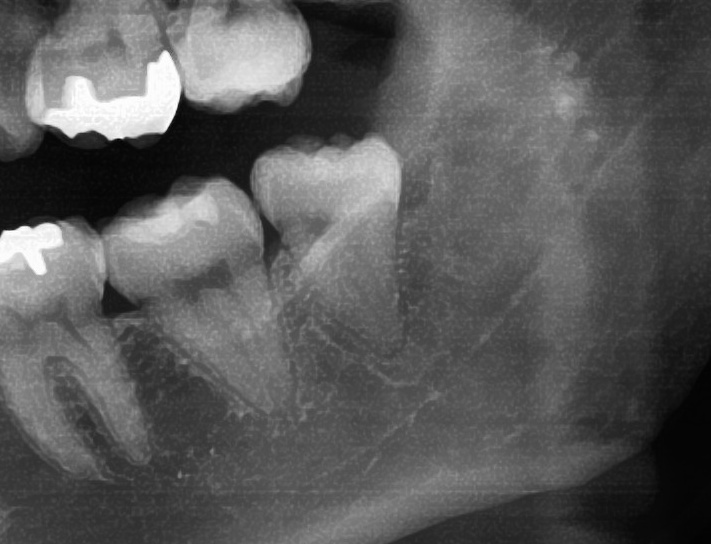

次にパノラマ写真を撮影してみると、左下の親知らずは手前の歯と並んでまっすぐに生えているのが確認できました。

親知らずが生えている位置が、神経に近い、あるいは神経に当たっている場合は、大きな病院に紹介する場合もあります。

親知らずの根っこは下歯槽神経からは十分距離があるようです。